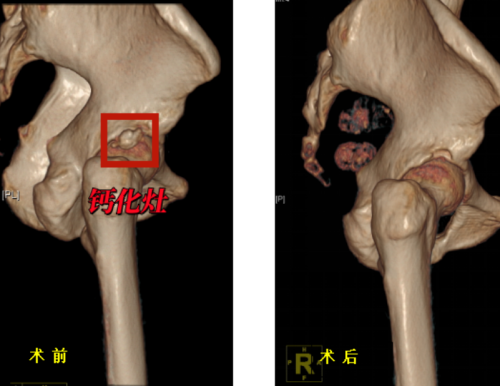

术前、术后三维CT对比示意钙化灶已清除

治疗方面,保守疗法包括药物止痛、物理治疗、局部注射等方法。但由于钙化灶的存在,保守治疗往往只能暂时缓解症状,难以彻底解决问题,手术治疗则是更为直接有效的选择。通过关节镜微创技术清除钙化灶,修复受损肌腱。该手术具有创伤小、恢复快、直视下精准操作、清除彻底,效果立竿见影、并发症少,安全性高等优点。

运动医学科门诊就诊,完善X线及核磁共振检查,考虑诊断为“右髋关节钙化性肌腱炎”并入院接受治疗。丑克主任团队为老人进行了髋关节镜微创手术,术后老人疼痛症状明显消退。老人开心地表示:“做完手术就不痛啦,效果立竿见影”。